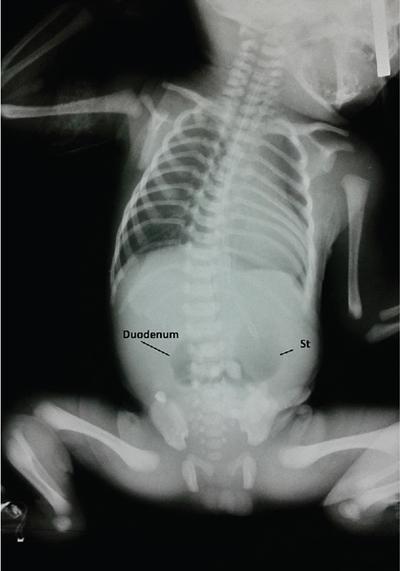

Duodenal atresia can result in bilious or nonbilious vomiting in the first 24 hours after birth.

The atresia is usually located distal to the ampulla of Vater. In complete atresia, no gas will pass distal to the duodenum and there will be collapse of the bowel loops.

Associated with polyhydramnios and VATER anomalies (vertebral defects, anal atresia, tracheo-oesophageal fistula with oesophageal atresia, radial and renal anomalies)

Plain radiograph shows the double bubble sign with no distal gas in the abdomen. The double bubble sign represents dilatation of the stomach and duodenum.

Note: When oesophageal atresia is associated with duodenal atresia, no air enters the stomach and the child presents with a large opaque midabdominal mass (representing the stomach).

Image

Fig. 7.4.1.2 Radiograph of the abdomen showing double bubble sign due to air distending the stomach and duodenum with no gas distal to the duodenum.